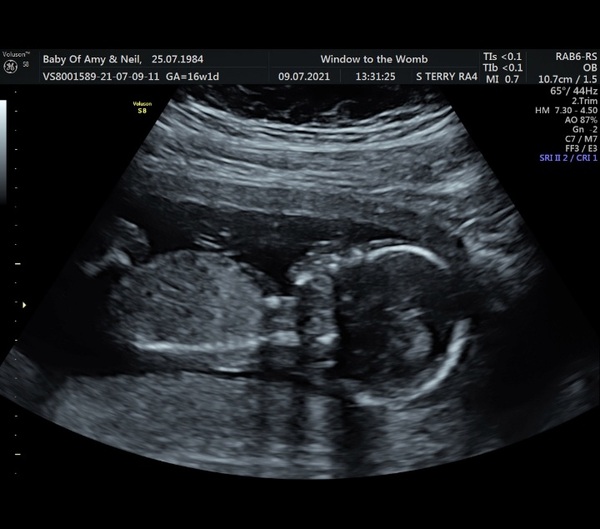

Bella1984 · 18/08/2021 14:28

Our wee peaceful lady at 19 weeks 🥰

Bella1984 · 18/08/2021 14:30

Actually that was our 16.5 week scan we had done privately, oops! She was a little bigger at 19 👌